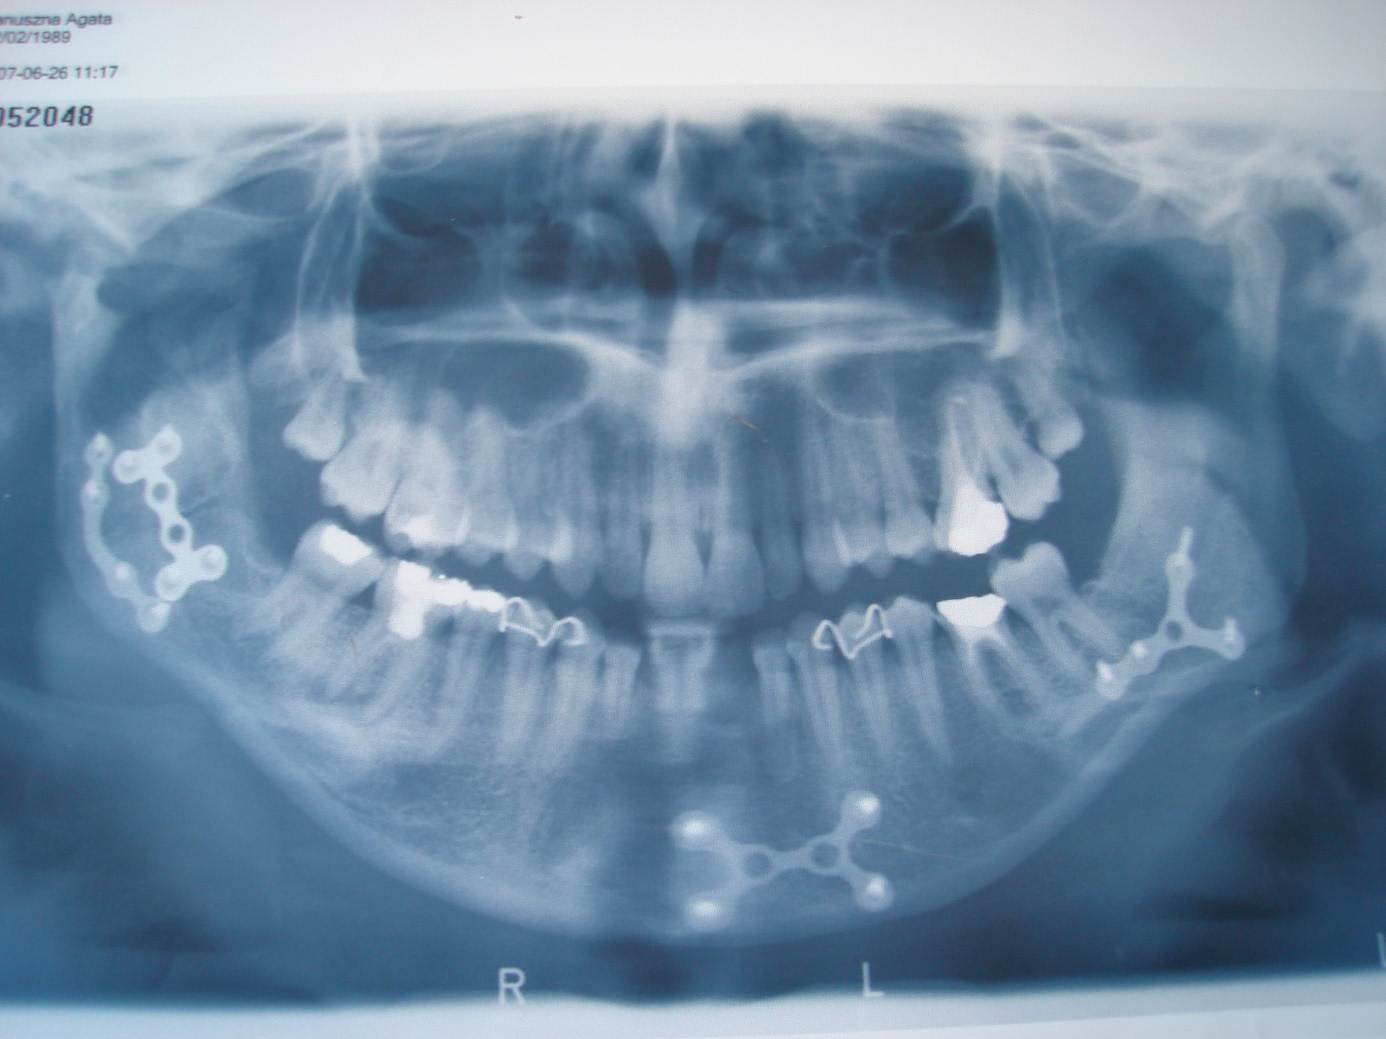

In 5 of the patients, the interincisal distance was of 27–30 mm. These patients complained about painful jaw opening limitation. Spontaneously implemented by these patients analgetic treatment was applied once a day in the morning, when the pain was the greatest. In these patients, the X-ray imaging results were revised and new CT scans were performed in three-dimensional (3D) reconstruction (Table 4). The rehabilitation technique applied earlier was maintained. After 52 weeks of rehabilitation, a jaw opening of 34–44 mm was recorded in these patients (Figure 1).

In patient XY, jaw opening improvement was taking place at the slowest rate. After 6 weeks of rehabilitation, 13 weeks post injury, jaw opening in the patient expanded from 10 to 27 mm. The late beginning of rehabilitation was associated with dislocation in TMJ, which primarily occurred due to a complex injury – a multi-fragmented fracture within the mental region, a bilateral fracture within the area of the mandible angles, a right-side fracture of the condyle process and the styloid process, with the knock-out of lower central incisors (Figure 2). The displacement of TMJ occurred for the 2nd and 3rd time in the patient, in whom the fragments of the mandible were stabilized through the use of ORIF, and finally permanent maxillomandibular fixation was applied after placing a partial mobile prosthesis in the oral cavity, which recreated lower central incisors. Anxiety about the renewal of the TMJ displacement probably retarded full commitment to rehabilitation.

Mouth opening lesser than expected by the patient is the main problem after a condylar process fracture. However, there are some jaw opening widths referred to as a norm; according to Agraval et al., it is 50 mm,16 and according to Cox and Walker, the minimum is 34 mm.17 A patient’s sensation that they can effortlessly or painlessly, and accordingly to their assumptions, open and close their mouth is the most important. The cause of mouth opening limitation may be directly associated with the injury effect. The limitation may also results in the necessity of applying intermaxillary fixation for some time. Determining the cause seems to be important for effective rehabilitation. Pre-surgical orthopantomograms and sagittal CT scans in the described group of patients seem to be insufficient for the assessment of the post-injury changes concerning the bony and soft elements of TMJ. Condylar process fractures are perceived by the authors specialized in the field as difficult for imagining due to the overlapping of many anatomical structures on the condylar process. An oral pantomogram, posteroanterior X-ray images of the mandible, and alternatively a lateral oblique view, are reliable imagining examinations implemented in the diagnosis of fractured craniofacial bones; CT, and especially CT in 3D reconstruction, are the methods of choice in the diagnosis of condylar process fractures.3, 18 According to Mueller et al., spiral CT gives a 100% chance of defining a mandible fracture, while panoramic tomography gives an 86% chance.19